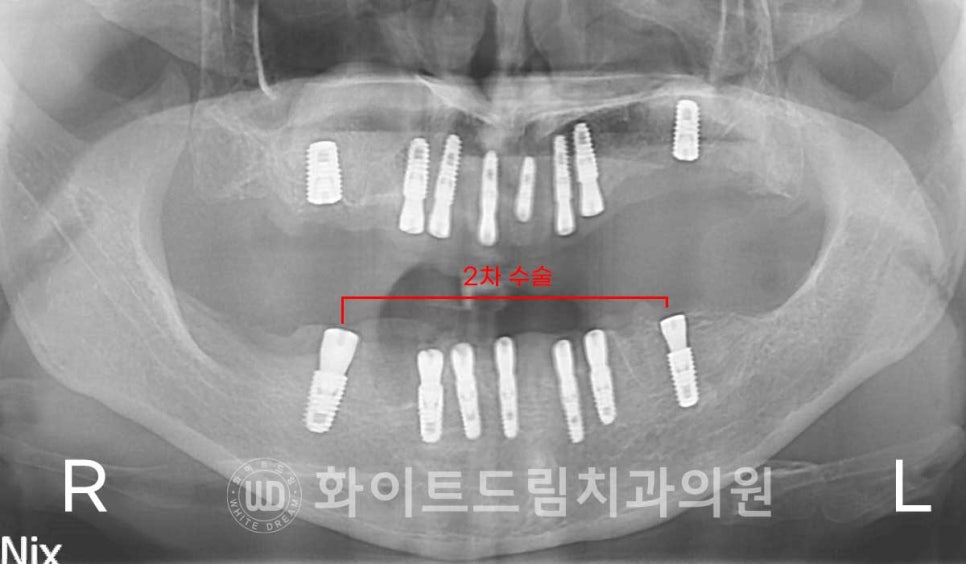

1차 수술과 2차 수술을 분리하여 진행할 경우

2-3개월의 회복 기간을 가진 후 2차 수술을 진행하게 됩니다.

즉시 식립이라고 해서

무조건 당일 모든 치료 과정을 한 번에 진행할 수 있는 것은 아니랍니다.

▲ 1차 수술 5개월 뒤, 2차 수술을 진행하게 됩니다. / 강남역전체임플란트 과정

(보통 3-4개월의 회복 기간을 갖는데 환자분은 많은 양의 뼈이식재가 들어간 상태라

2개월의 회복 기간을 추가로 두게 되었답니다. )

▲ 하악은 골질, 잔존 골의 상태가 상악보다는 양호해

2차 수술까지 한 번에 진행을 하게 되었답니다. ^^